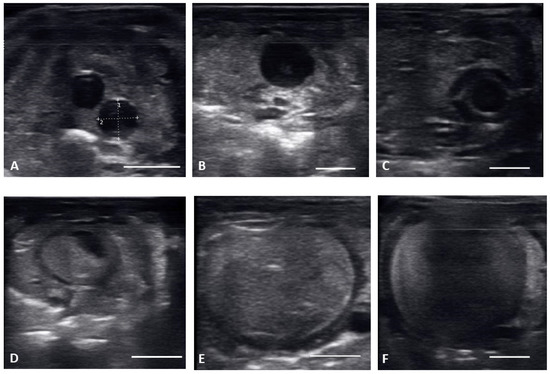

| Previtellogenic Follicles (PVF) | Anechoic Follicles, Small and Rounded, String-Aligned |

|---|---|

| Early vitellogenic follicles (EVF) | Small, round follicles showing hyperechoic outline around an anechoic middle and hyperechoic center. |

| Vitellogenic follicles (VF) | Oval shaped follicles showing a thickening hyperechoic outline as granulosa cell layer increase, hyperechoic ooplasm, and an anechoic core centrally located. |

| Preovulatory follicles (PrOV) | Elongating and increasing hyperechoic ooplasm as follicles are filled with yolk, with an elongated anechoic area located in the periphery of the ooplasm. |

| Peri-ovulatory follicles (PERI) | Elongated follicles, mostly homogenous hyperechoic structure with thick hypoechoic outline. Before female is overtly swollen. |

| Post ovulatory follicles (POV) | Ovulated follicles, passed into the oviduct showing an hypoechoic surrounding, but no visible calcified layer. |

| Shelled eggs (Shell) | Ovulated follicles, passed into the oviduct and surrounded by a calcified layer. |